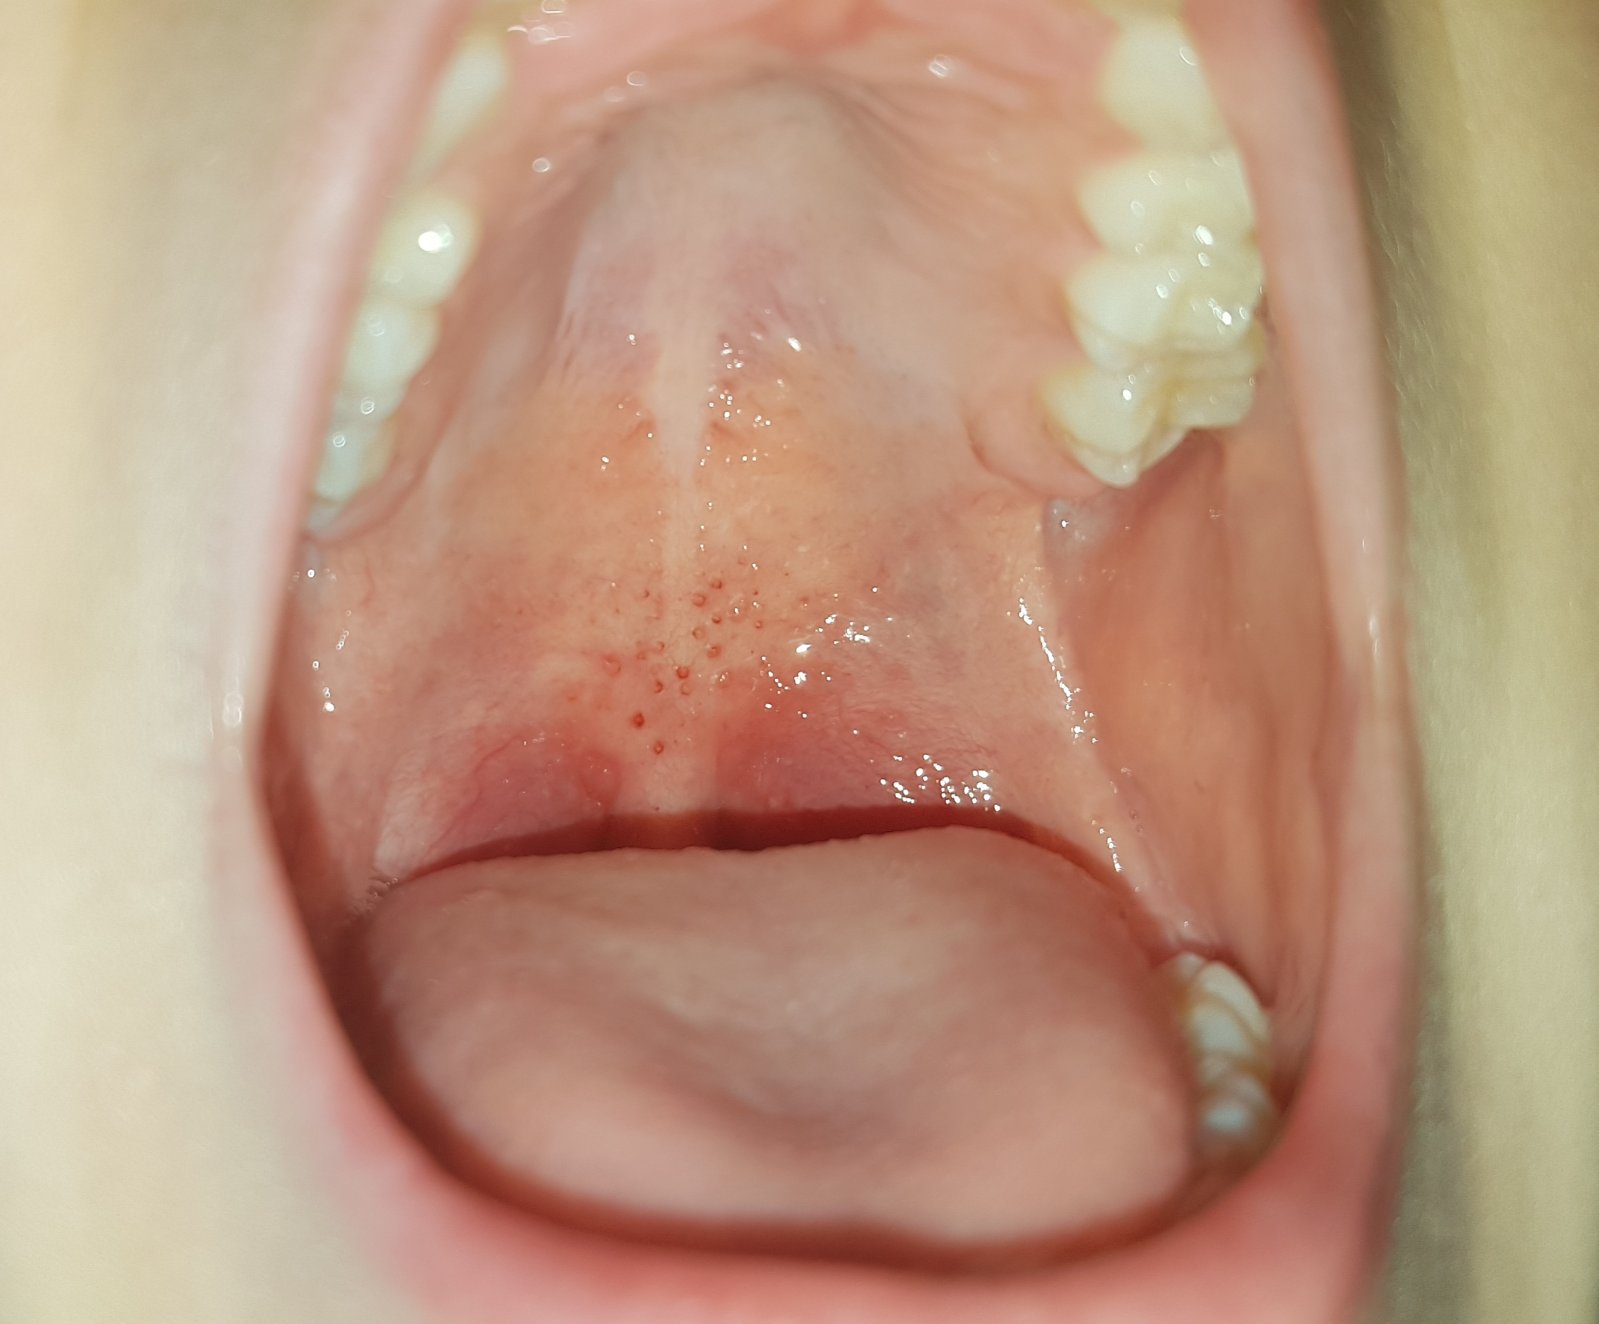

Pozná někdo, co to je? Samozřejmě zítra jdeme k MUDR.

Dcera, 9 let, stěžuje si, že ji to v puse svědí a jinak je O.K., má rýmu, jinak je v pořádku.

To vypadá jako zdurely, otekly patro k ty rýmě. Zánět nosohltanu... nebo streptokok. A začínající angina. Nebo úplně něco jinyho.... :D Diagnoza z fotky. Moje oblíbená. ;) at vám to dobre dopadne !

Mela uz nestovice? Ty pupinky se muzou objevit i na sliznici. Jinak nevim, kazdopadne dej vedet, co zitra zjistite, zajima me, co to je 😀

Dcerka tohle má vždy k začínající rýmě. 🤷‍♀️